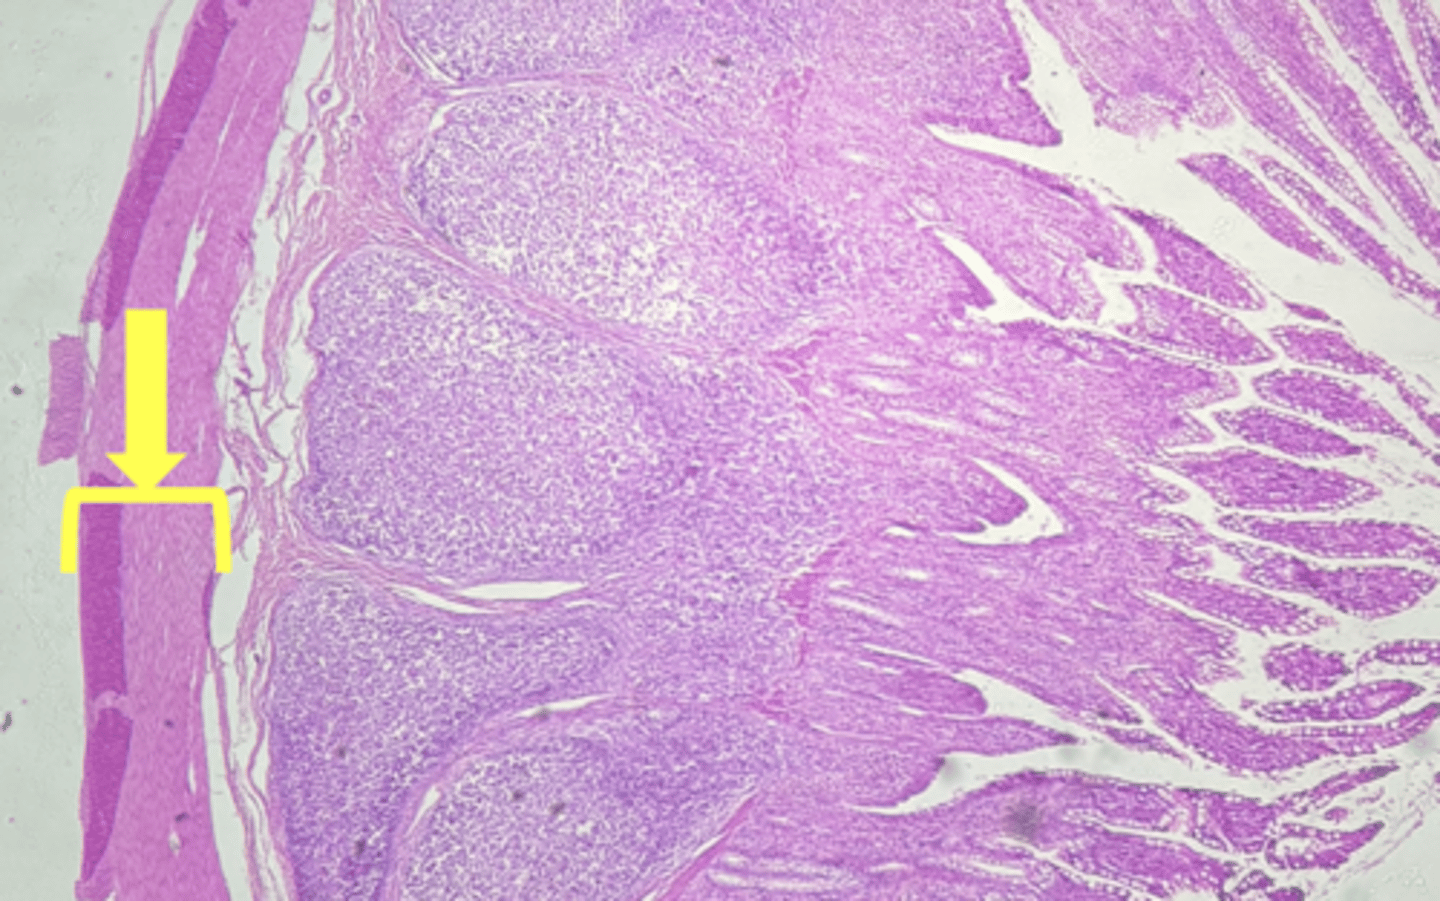

colon- large intestine

name the tissue

circular layer

(Lg. intestine)

longitudinal layer

mucosa

(lg intestine)

Submucosa

muscularis externa

goblet cells-mucus (LARGE # KEY CHARACTERISTIC)

name the cell & what it secretes

intestinal crypts

muscularis mucosae